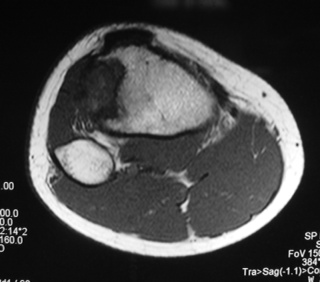

MRI (Fig. 4-7)

• Central low signal intensity with peripheral enhancement on T1-weighted images

• Heterogeneous high signal intensity with low signal in surrounding sclerotic bone on T2-weighted images

Fig. 4

Fig. 4-7: MR imaging of a benign fibrous histiocytoma of the proximal tibia demonstrates a heterogeneous high signal intensity and low signal intensity with surrounding sclerotic bone on T2-weighted images. T1-weighted images show low signal intensity. No soft tissue mass is visible.